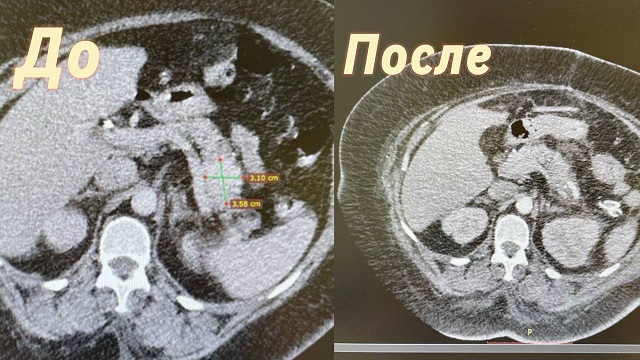

Фотографии медицинских исследований инсулиномы и синдрома Триады Уиппла